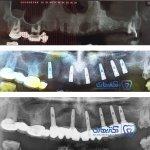

همچنین ایشان در دی ماه سال 2013 میلادی سرتیفیکیت دوره پیشرفته ایمپلنت های دندانی را دریافت کردند. علاوه ازاین، اخیرا در پی تلاش برای بروز رسانی اطلاعات علمی و همگامی با دانش روز دنیا سرتیفیکیت دوره پیشرفته جراحی و درمان ریشه دندان (عصب کشی) را در سال 2016 میلادی از دانشگاه جنوا ایتالیا دریافت کرده اند.

گالری